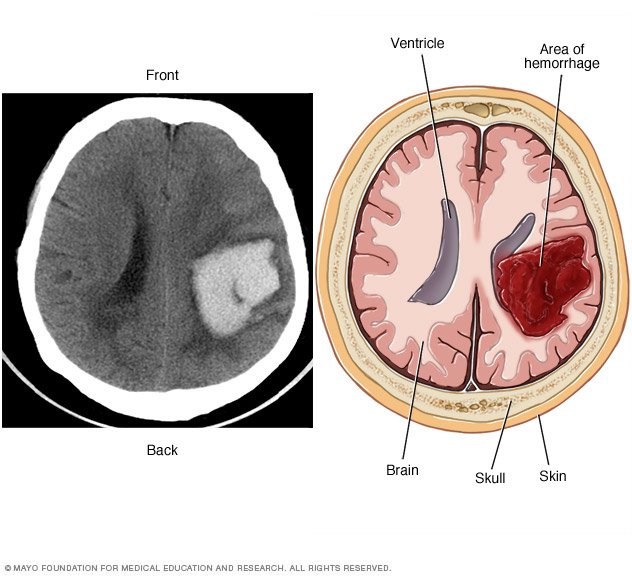

نزيف المخ أو الدماغ هو نوع من أنواع السكتة الدماغية وهو ناجم عن فتق شريان في الدماغ يتسبب في نزيف موضعي في الأنسجة المحيطة مما يؤدي إلى حدوث نزيف يقتل خلايا الدماغ.

هل نزيف الدماغ يسبب الوفاة. هل نزيف الدماغ يسبب الوفاة. هل نزيف الدماغ يسبب الوفاة كثير ا ما نسمع مثل تلك العبارات بعد رؤية حالة وفاة مفاجأة بسبب السكتة الدماغية والتي تكون نتيجة متوقعة نزيف الدماغ الداخلي الذي يسببه الانفجار المفاجئ للدم في منطقة معينة من الدماغ مما. هل نزيف الدماغ يسبب الوفاة وما مدى الشفاء منه موضوعنا اليوم عن نزيف الدماغ حيث يهتم الكثيرون بمعرفة بعض أسبابه أعراضه وهل نزيف الدماغ يسبب الوفاة أم لا وما مدى الشفاء منه وهذا ما نتناوله اليوم بشئ من التفصيل في هذا. هل نزيف الدماغ يسبب الوفاة نعم بالفعل نزيف المخ يسبب الموت في كثير من الحالات التي تتعرض له وذلك لأن حالات النزيف في المخ تحتاج في أغلب الأحيان إلى إجراء جراحة عاجلة لوقف هذا النزيف حتى لا.